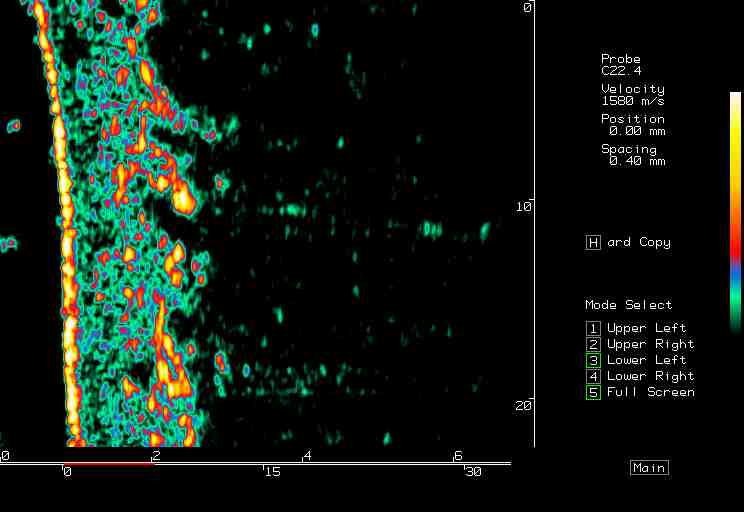

20 MHz 2D images

| Tumors |  BCC on the ear |

BCC, various sites |

BCC pre PDT |

BCC post PDT |